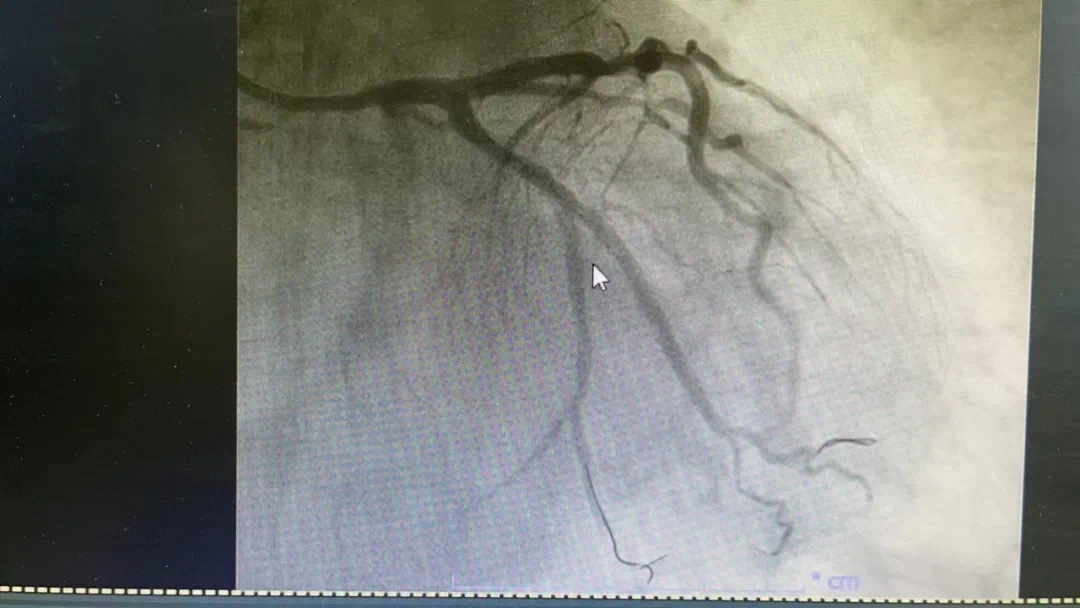

副主任何涛、医师熊俊锋、护士张梅梅顾不上休息,立刻投入到第三次抢救中。胸痛中心团队心内科与急诊科无缝衔接,23点26分在导管室开通堵塞血管,又成功救治一名急性心肌梗死患者。患者张某送至导管室施行急诊冠脉介入治疗,经过快速的术前准备,以mini Crush术式于回旋支远段植入波科冠脉支架一枚,再于钝缘支中段至回旋支中段植入Firebird2冠脉支架一枚。患者症状大幅缓解。零点42分手术结束,复查患者血压、心率正常后将患者送回病房。

术前、术后图片如下